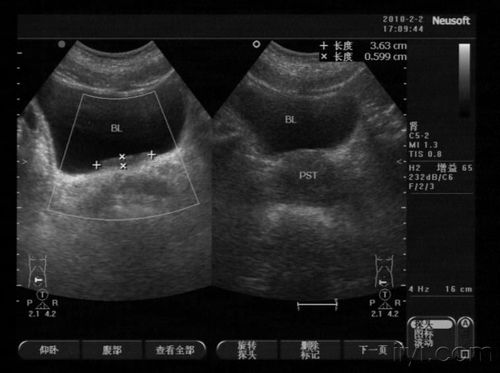

膀胱顶占位性病变?

膀胱占位

典型膀胱占位两例!(膀胱癌)

这是膀胱占位吗?